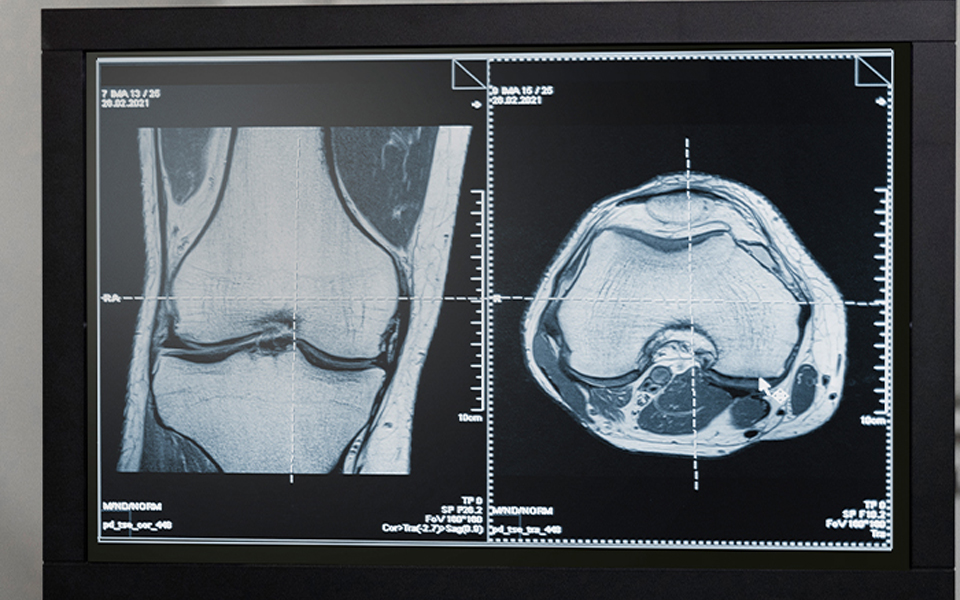

However, another medical device developed for neurosurgery is based on advanced imaging technologies that allow surgeons to get a better view during the surgical procedure. This technology can help surgeons access brain tissue using smaller and less invasive incisions, which can speed up the healing process of surgical interventions and improve patient comfort.